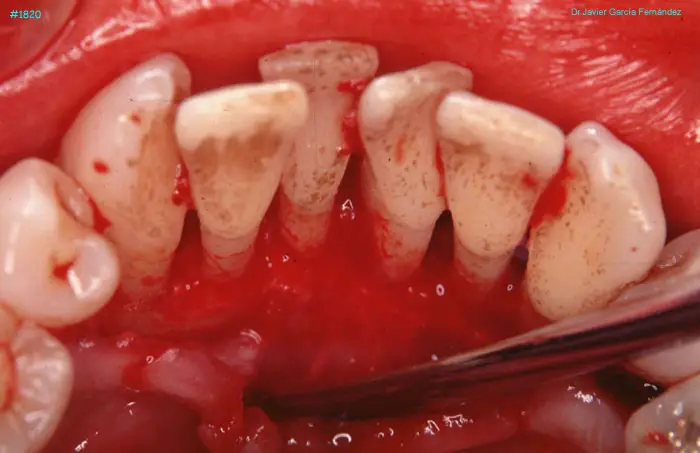

image 86